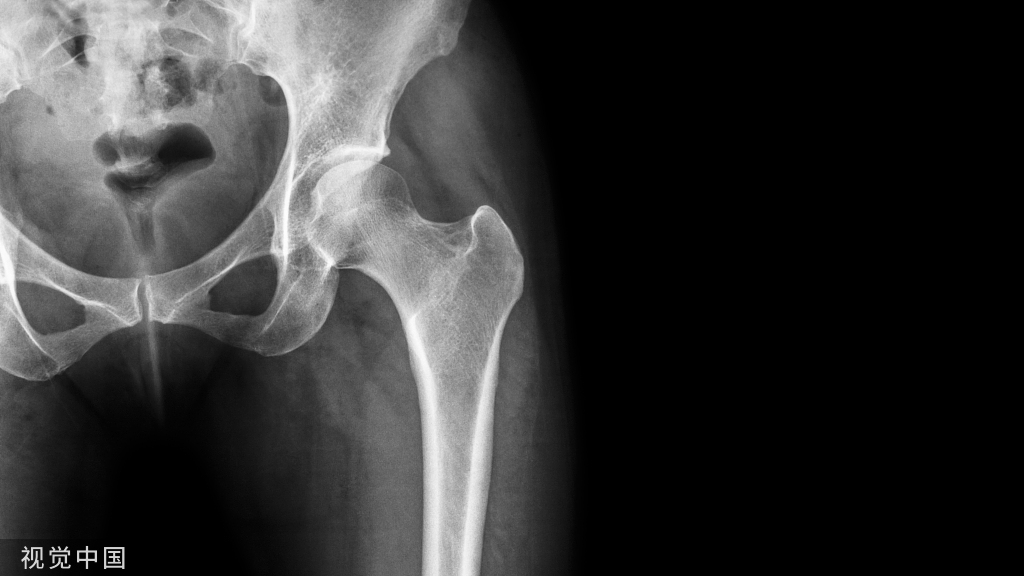

骨盆的X线解剖

骨盆一般投照前后位,检查骶、尾骨时可加照侧位,检查骶髂关节时应加照45°斜位,产科骨盆测量另有其特殊投照方法。

骨盆前后位片上,骶骨中线应通过耻骨联合。骶髂关节左右对称,关节间隙下半部分可以显示,上半部常投影出模糊双线影。界线的影像在女性呈卵圆形,在男性略呈鸡心形。髂嵴连线影正好通过第4、5腰椎间隙。

由髂嵴影向外可追踪到骼前上、下棘,由髂前下棘到股骨颈外上缘的连线称髂颈线,用以判定髋关节是否正常。正位片上,可以测量耻骨下角,男性为锐角,女性为钝角。

女性骨盆径线的测量,可以采用正位(见图1)和侧位。正位片上,界线影像最远点连线为入口横径,正常为12.3cm;两侧坐骨棘连线为中骨盆横径,正常为10.5cm;两侧坐骨结节间距为小骨盆出口横径,正常为11.8cm。